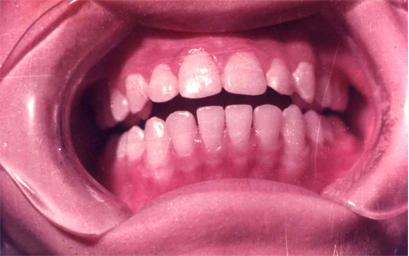

儿童牙齿发育过程中摄入过量的氟会引起氟斑牙:

可疑:上中切齿唇面有白色薄雾状或条状白色横纹

极轻度:上中切齿唇面有条状白色斑纹,占牙面1/4以下。

轻度:白色条纹或斑块,占牙面1/2以下,可出现浅棕色着色。

中度:上中切齿或全口牙整个牙面出现白垩,失去光泽,有明显着色。有的出现小点状凹坑。

重度:全口牙面呈白垩,出现散在坑凹状缺损或融合成片状缺损,有较重的着色。